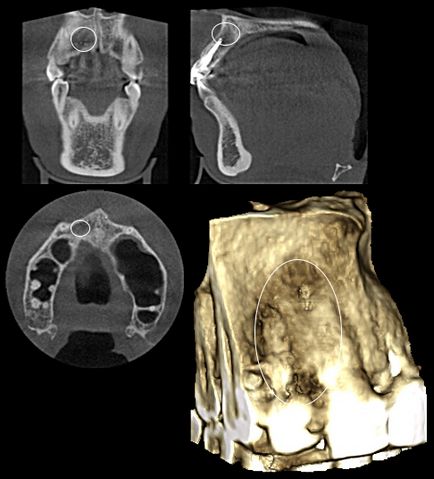

Ciszta maxillaris fog, fogeredetű arcüreggyulladás

Hely bölcsességfog gyökerei az arcüreg